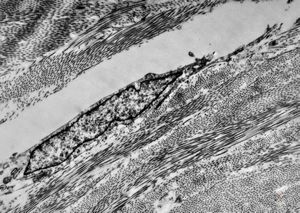

F,41y. | synovial metaplasia - capsule of implantate

F,41y. | synovial metaplasia - capsule of implantate

F,41y. | synovial metaplasia - capsule of implantate

F,41y. | synovial metaplasia - capsule of implantate

F,41y. | synovial metaplasia - capsule of implantate

F,41y. | synovial metaplasia - capsule of implantate

F,41y. | synovial metaplasia - capsule of implantate

F,41y. | synovial metaplasia - capsule of implantate

F,41y. | synovial metaplasia - capsule of implantate